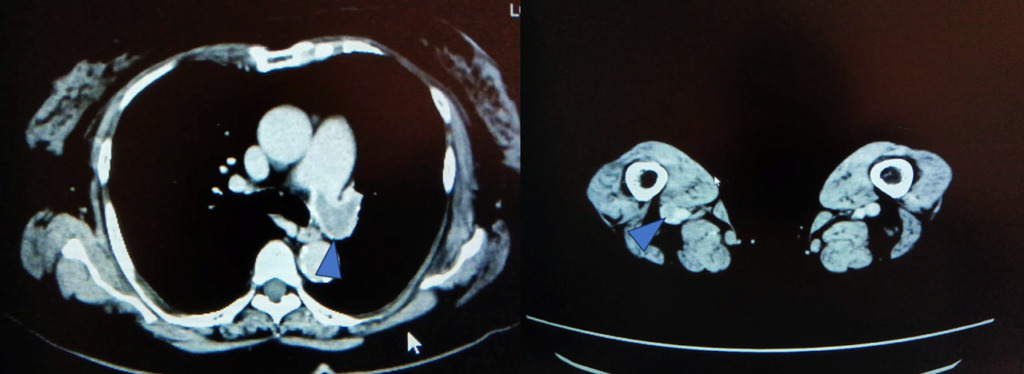

低電圧CT撮影について

120kvで撮影した時の造影剤のCT値を1とした時の相対値では低電圧にするとCT値が1.6と上がり、120kvでの撮影した時と同じ造影効果を得るために必要な造影剤量も62%と減らせます。

実際の画像ですが、

120kV と比べるとCTは上がっていることがわかります。

当院の臨床画像でも

80kvで撮影した方がDVTの描出が良くなっています。

その他にも低電圧で撮影するので光子量が減るため、被ばく量が少なくなるというメリットもありますが、ただし注意が必要なのは電圧を下げることによって透過するエネルギーが低くなるので120kvと比較するとノイズが多くなります。